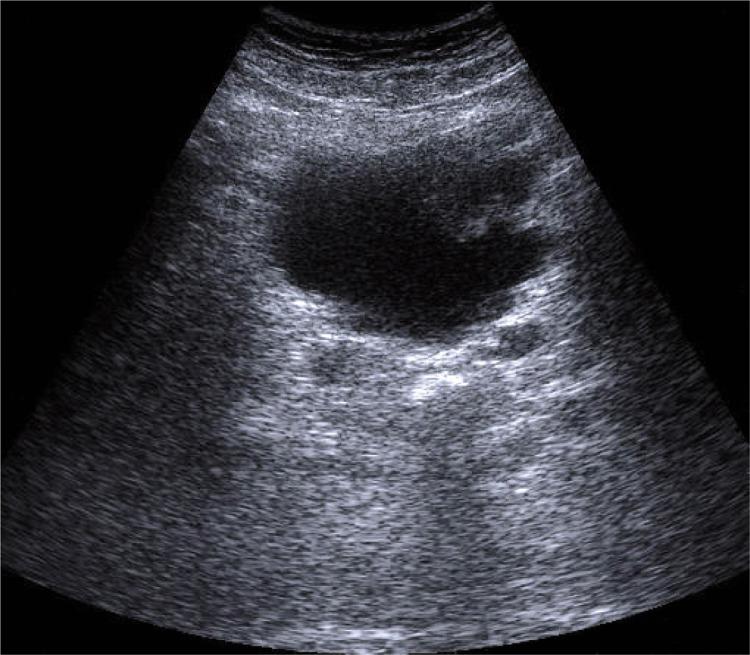

The paper presents the principles of performing proper ultrasound examinations of the urinary tract. The following are discussed: preparation of patients, type of optimal apparatus, technique of examination and conditions which its description should fulfill. Urinary track examination in adults and in children constitutes an integral part of each abdominal examination. Such examinations should be performed with fasting patients or several hours after the last meal, with filled urinary bladder.

Renal examinations are performed with the patients in the supine position. The right kidney is examined in the right hypochondriac region using the liver as the ultrasound "window." The left kidney is examined in the left hypochondriac region, preferably in the posterior axillary line. Ultrasound examinations of the upper segment of the ureters are performed after renal examination when the pelvicalyceal system is dilated. A condition necessary for a proper examination of the perivesical portion of the ureter is full urinary bladder. The scans of the urinary bladder are performed in transverse, longitudinal and oblique planes when the bladder is filled.

本文介绍了对尿路进行正确超声检查的原则。讨论了以下内容:患者准备、最佳设备类型、检查技术以及检查描述应满足的条件。成人和儿童的尿路检查是每次腹部检查的组成部分。此类检查应在患者空腹或最后一餐数小时后进行,膀胱需充盈。

肾脏检查时患者取仰卧位。右肾在右季肋区检查,以肝脏作为超声“窗口”。左肾在左季肋区检查,最好在腋后线。当肾盂肾盏系统扩张时,在肾脏检查后对输尿管上段进行超声检查。对输尿管膀胱周围部分进行正确检查的一个必要条件是膀胱充盈。膀胱扫描在膀胱充盈时在横切、纵切和斜切平面进行。